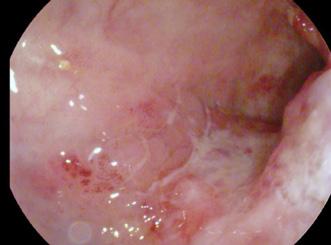

În iulie 2018, pacientul a revenit la control, normoponderal (IMC 20,6 kg/ m2), fiind în remisiune clinică, iar bi ologic în limite normale. S-a efectuat o reevaluare colonoscopică la care s-au identificat pseudopolipi și leziuni cica triceale postinflamatorii la nivelul între gului colon, iar la 25 cm de orificiul anal, un ulcer cu diametrul de 20 mm (Figura 1), din care s-au prelevat multiple biopsii. Aspectul histologic a relevat adenocar cinom colonic moderat diferențiat. La examinarea CT toraco-abdomino-pelvin, s-au vizualizat micronoduli pulmonari nespecifici, o îngroșare parietală la ni velul ceco-ascendentului cu aspect infla mator și o îngroșare parietală asimetrică la nivelul joncțiunii recto-sigmoidiene, sugestivă pentru un substrat tumoral (Fi gura 2).

Figura 1. Leziune decelată colonoscopic la 25 cm de OA Figura 2: Îngroșare parietală asimetrică la nivelul joncțiunii recto-sigmoidiene Figura 3. Adenocarcinom moderat diferențiat, cu arhitectură tubulară